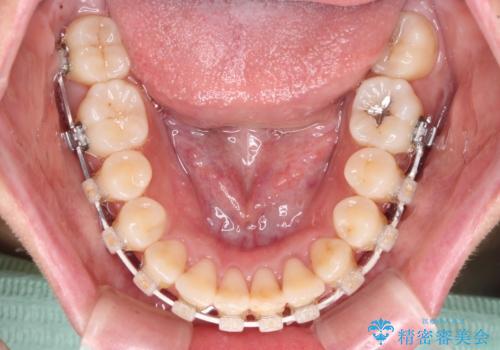

前歯のクロスバイト 目立たないワイヤー装置で速やかに矯正治療

- 審美装置

治療前にお伝えした治療期間は1~1年半でして、1年4か月の期間で終えることができました。

ワイヤー矯正は見た目や装置が当たることでの痛みを気にされる方が多いですが、月1回来院して処置をしてもらうだけで歯並びが整うため、大変お勧めです。